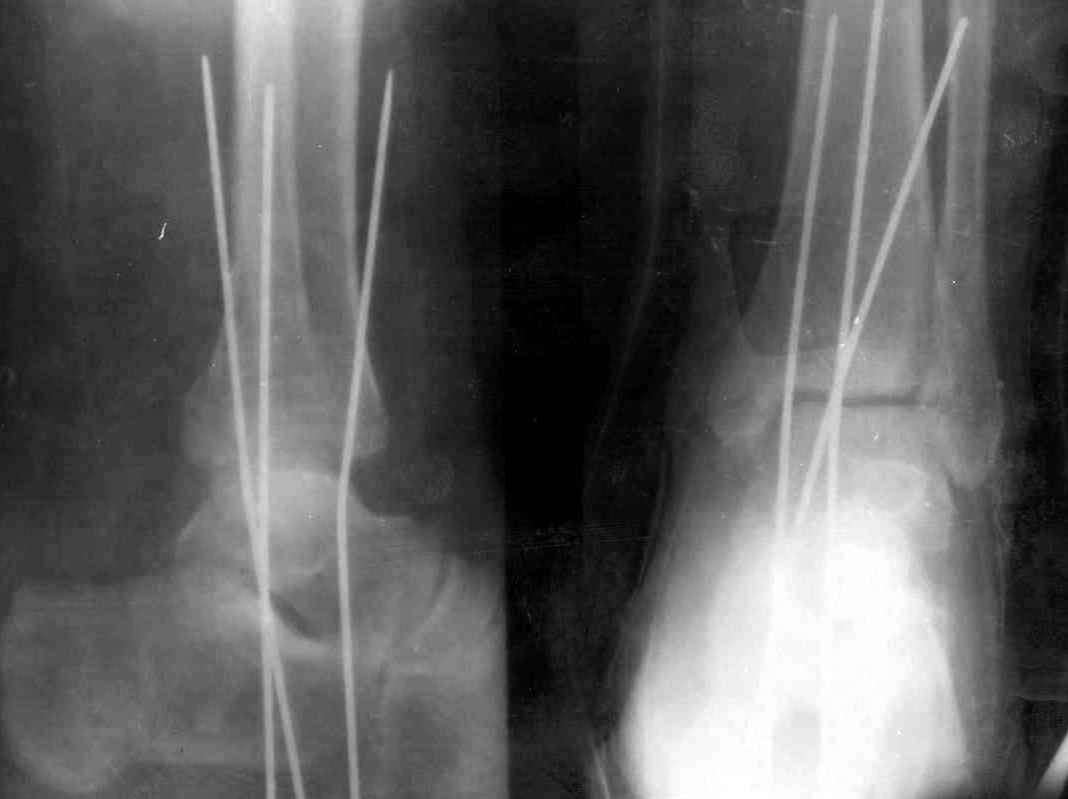

После проведенной дискуссии пришел к выводу, что трансартикулярная диафиксация не совсем приемлима с учетом современных методик остеосинтеза. Кроме того, вычитал, что хрящ разрушается на расстоянии до 0,5 см от места проведения спицы.

Пока я был в интернатуре, предпочитали осуществлять стабильный остеосинтез с ранней функцией. См. приложения и полнотекстный вариант

статьи.